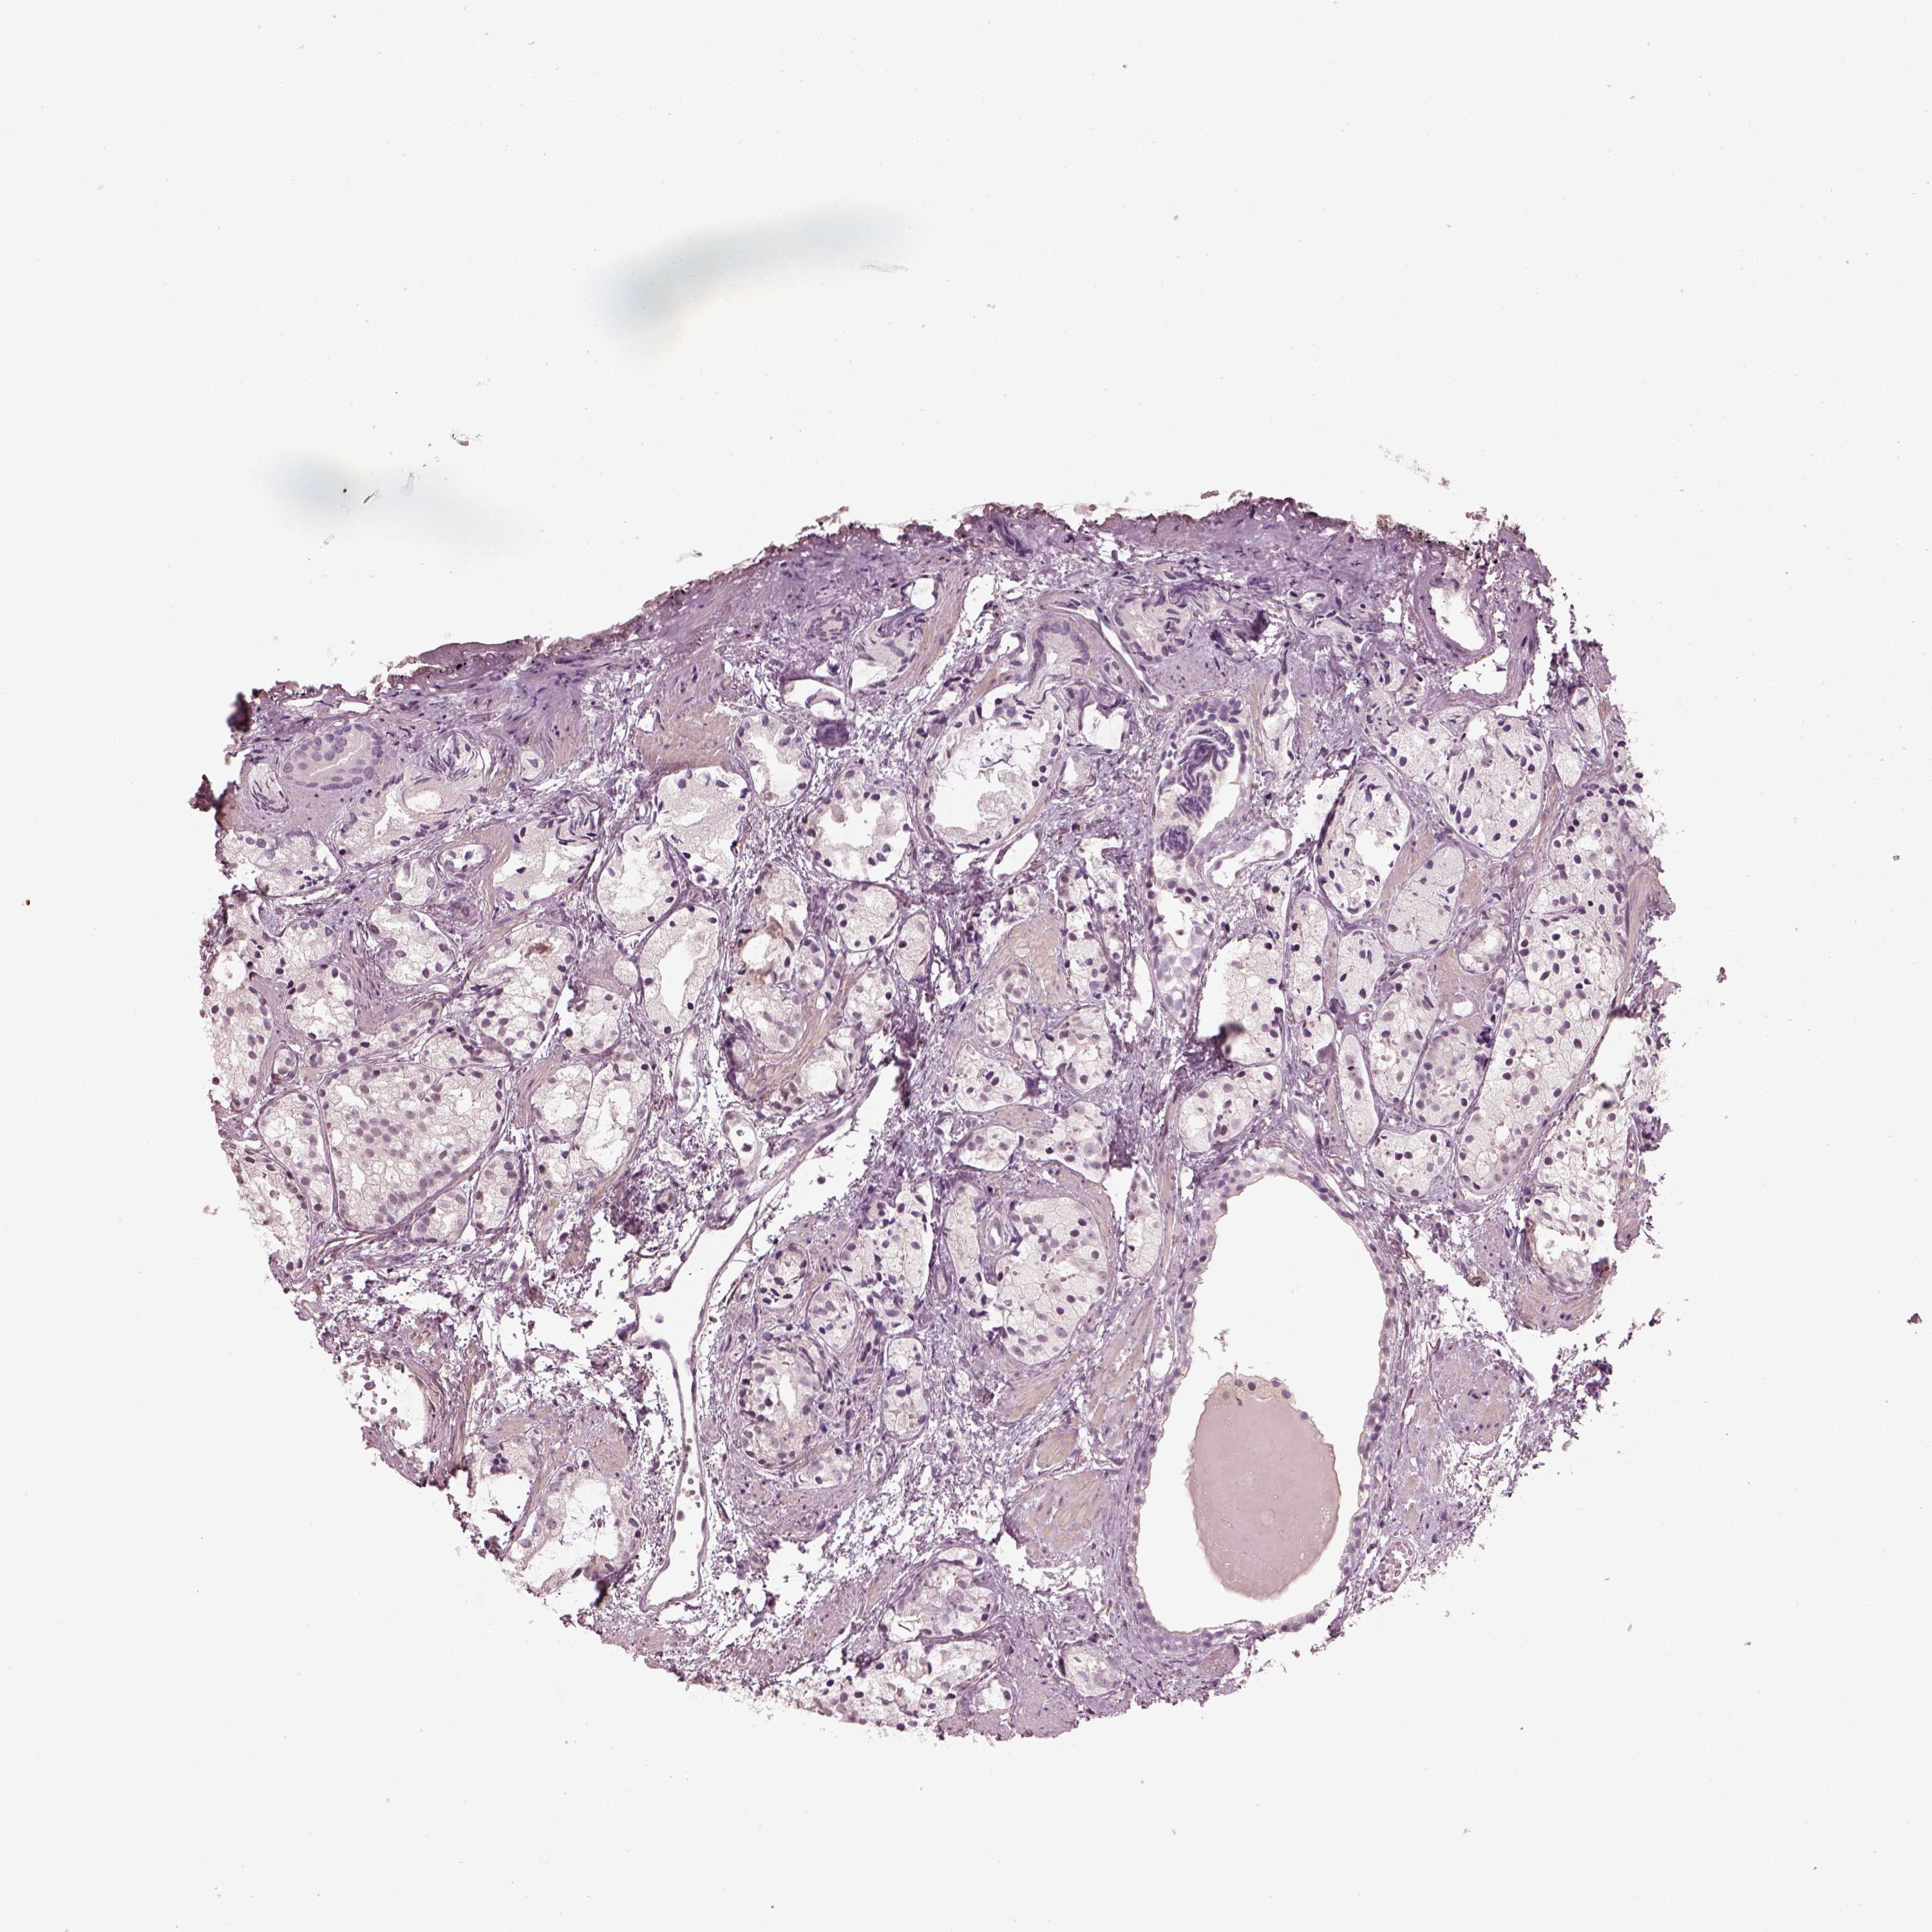

PROSTATE CANCER - Protein expressioni

A mouse-over function shows sample information and annotation data. Click on an image to view it in a full screen mode. Samples can be filtered based on level of antibody staining by selecting one or several of the following categories: high, medium, low and not detected. The assay and annotation is described here.

Note that samples used for immunohistochemistry by the Human Protein Atlas do not correspond to samples in the TCGA dataset.

Antibody stainingi

Antibody staining in the annotated cell types in the current human tissue is reported as not detected, low, medium, or high, based on conventional immunohistochemistry profiling in selected tissues. This score is based on the combination of the staining intensity and fraction of stained cells.

Each image is clickable and will lead to virtual microscopy that enables deeper exploration of all samples and also displays staining intensity scores, fraction scores and subcellular localization as well as patient and tissue information for each sample.

Antibody HPA034951

Antibody HPA034952

Adenocarcinoma, High grade

Adenocarcinoma, NOS

Adenocarcinoma, Low grade